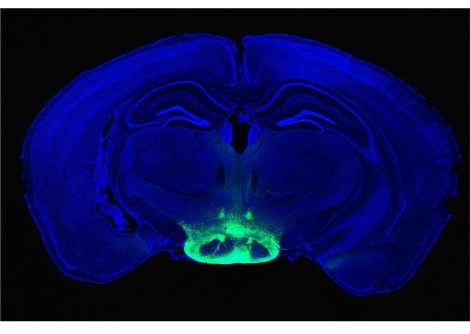

الآن ، تعمق هو وزملاؤه لمعرفة ما إذا كان هذا المسار من القناة الهضمية إلى المبهم يميز بين السكر والمحليات الاصطناعية ، وإذا كان الأمر كذلك ، فما هي الآليات العصبية التي يقوم عليها هذا التمايز. قام الفريق بتخدير الفئران ، وإرواء السكروز أو السكرالوز مباشرة في أحشائهم ، ثم قاموا بتحليل استجابة الخلايا العصبية التي تشكل العصب المبهم باستخدام تصوير الكالسيوم. في المتوسط ، استجاب 40.7 في المائة للسكروز فقط ، و 22.2 في المائة للسكرالوز (sucralose) فقط ، والباقي لم يستجيب لأي من المحفزين ، موضحين كيف أن العصب المبهم قادر على التفاعل بشكل مختلف مع المادتين.

تركت النتائج مفتوحة السؤال عما إذا كانت العصبونات تساهم في سلوكيات مختلفة استجابة للسكريات مقابل المحليات الاصطناعية. للإجابة على ذلك ، لجأت المجموعة إلى علم البصريات الوراثي ، وهي منهجية تستخدم في الغالب في الدماغ. قام الباحثون بتغيير الفئران وراثيًا بحيث يؤدي التعرض لأطوال موجية معينة من الضوء إلى إسكات خلايا الأرجل العصبية التي يتم تحفيزها عادةً بواسطة السكريات والمحليات ، بينما يحفزها الآخرون ، ومع ذلك لن يكون للآخرين أي تأثير ويسجلون كيف يؤثر ذلك على تفضيلات الفئران. كانت المشكلة أن توصيل الضوء يتطلب تقليديًا كابل ألياف بصرية سيليكا صلبًا ، والذي من شأنه أن يخترق الأنسجة الرخوة للأمعاء المتماوجة باستمرار. لذلك ، تعاون الباحثون مع المهندسين لتطوير كابل ألياف بصرية مرن يتكيف مع الظروف البيولوجية الفريدة للأمعاء ، كما يقول Bohórquez.